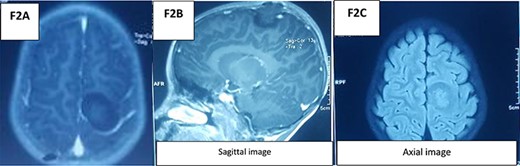

An MRI spine (Fig. 1) with the coronal slide detected two tumors, first in the intradural and intramedullary space at the C2–C4 level and the second in the intradural and extramedullary space at the C5–C7 level. Sagittal T1W contrast MRI spine revealed another enhanced broad-based intradural/extramedullary space at the C6–C7 level. Axial T1W contrast MRI brain (Fig. 2) showed a tumor in the left parietal region.